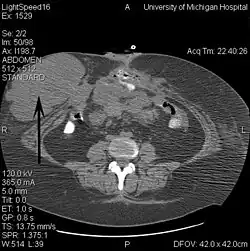

- Tomografia komputerowa

Tomografia komputerowa (TK) jest przydatnym narzędziem w diagnostyce guza desmoidalnego. Pozwala rozpoznać obecność litego guza w obrębie tkanek miękkich, określić jego lokalizację i rozmiar[5]. Jest pomocną metodą w diagnostyce powikłań guza związanych z jego lokalizacją[50]. W tomografii komputerowej guz desmoidalny jest słabo widoczny, ponieważ guz jest izodensyjny lub lekko hipodensyjny względem mięśni. Zmiana ze względu na bogate unaczynienie naczyń włosowatych ulega wzmocnieniu kontrastowemu[50][51]. Ze względu na inwazyjny wzór wzrostu marginesy zmiany mogą być słabo odgraniczone[50].